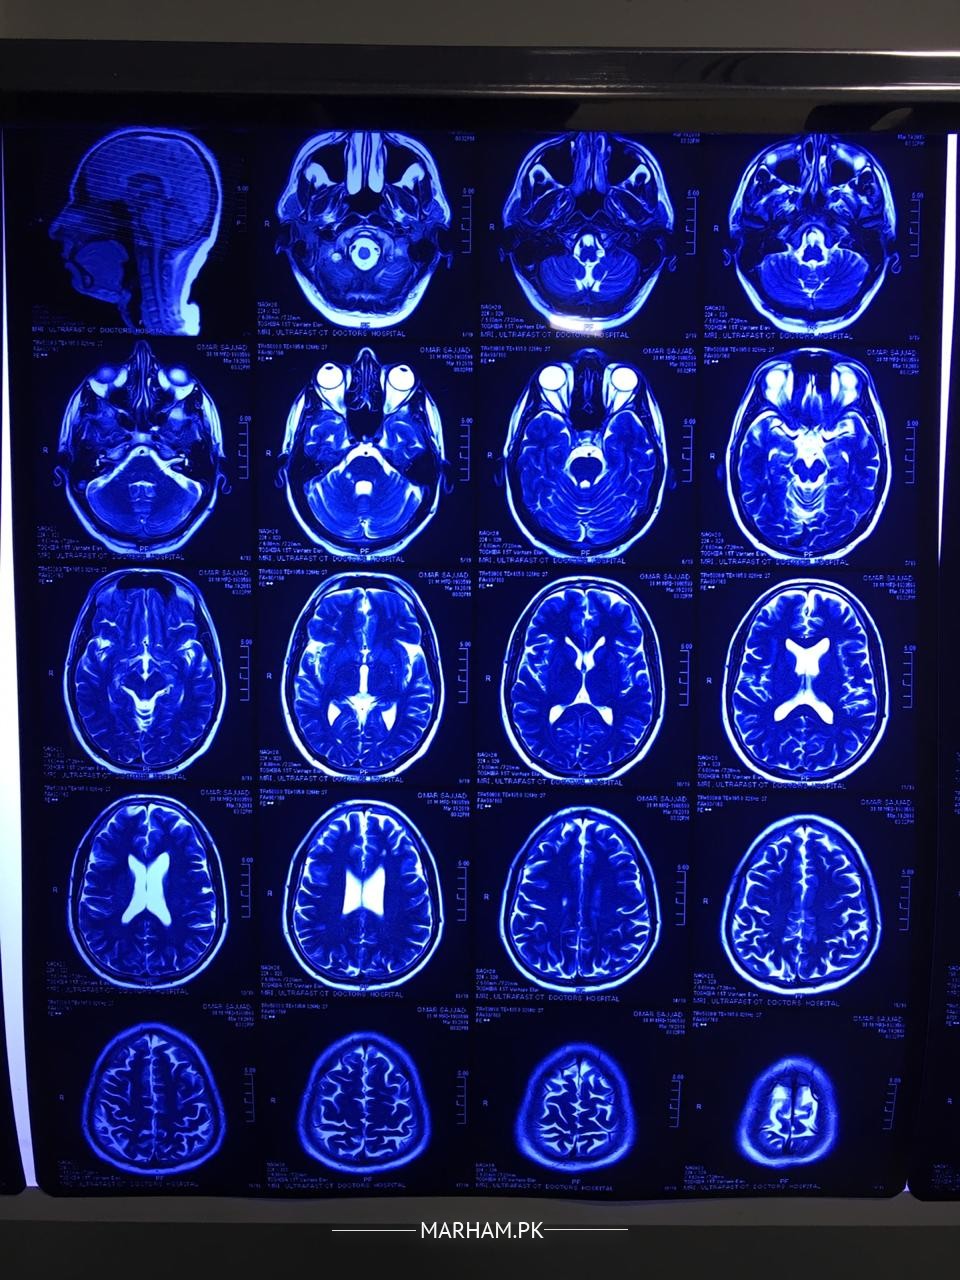

my husband had numbness in his right side of face half head. we consulted a doctor he recommended some tests and MRI. i m attaching some images plz help us understand what is the issue. m attaching all reports and images.

He is a young man and the MRI reports reveal a disease called as Multiple Sclerosis. It a disease in which body's own immune or defence system starts working against own brain tissues. It requires thorough investigations including Lumbar puncture, taking sample of fluid of brain from the spine , and few more tests. It is a chronic disease and you need to consult a neurologist so that appropriate plan of treatment can be discussed in detail.

The MRI scan report seems to suggest a diseases called Multiple Sclerosis. the dis have a deep blue tinge, therefore cannot be reliably commented upon. First the diagnosis needs to be confirmed, with contrast MRI scan and some other tests. then if it's really multiple Sclerosis then a Neurologist will discuss treatment options with you. there are good options available now to control the disease. however, I repeat , most importantly the diagnosis must be confirmed. for that you need to see a neurologist. neurological history and examination are as important as lab tests to diagnose this condition. please show a Neurologist in your city

mri brain finding are suggestive of most likely multiple sclerosis. a disease of demyelinating in nature . need detail history about your husband .